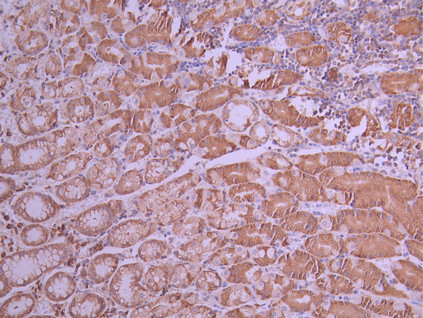

IHC image of CSB-RA258376A0HU diluted at 1:100 and staining in paraffin-embedded human gastric cancer performed on a Leica BondTM system. After dewaxing and hydration, antigen retrieval was mediated by high pressure in a citrate buffer (pH 6.0). Section was blocked with 10% normal goat serum 30min at RT. Then primary antibody (1% BSA) was incubated at 4°C overnight. The primary is detected by a Goat anti-rabbit polymer IgG labeled by HRP and visualized using 0.05% DAB.